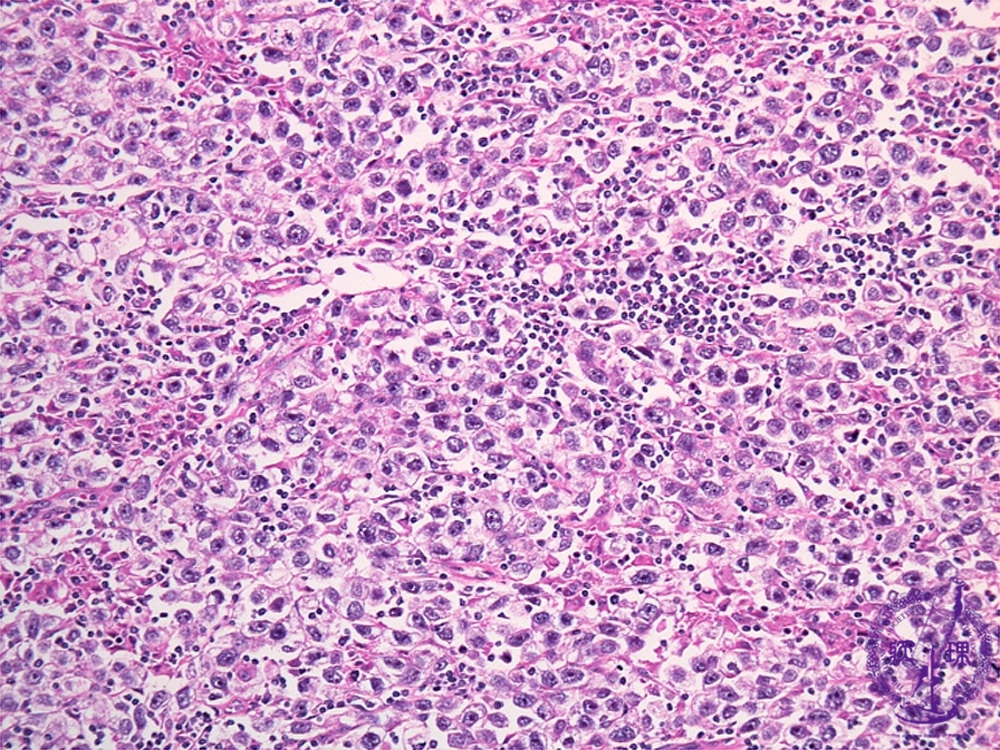

胎児性癌

胎児性がん細胞は、顕微鏡で見ると初期段階の胎児に見られる組織のように見えます。それらは次の場所で見つかります。

胎児性癌は進行性の癌です。これは、急速に成長し、広がる可能性があることを意味します。